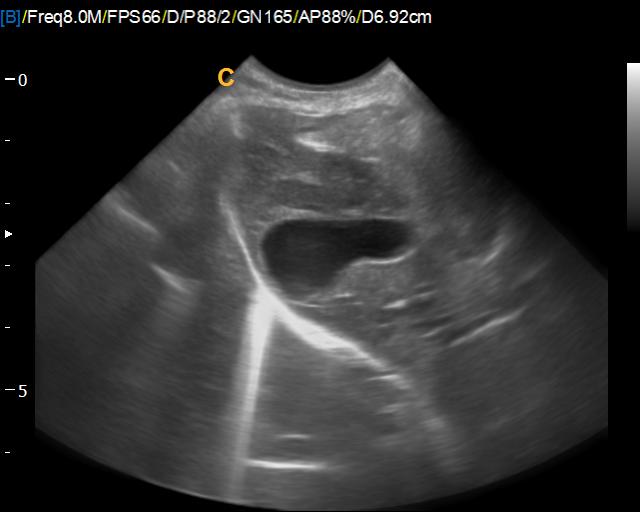

USG vyšetrenie a diagnostika gravidity